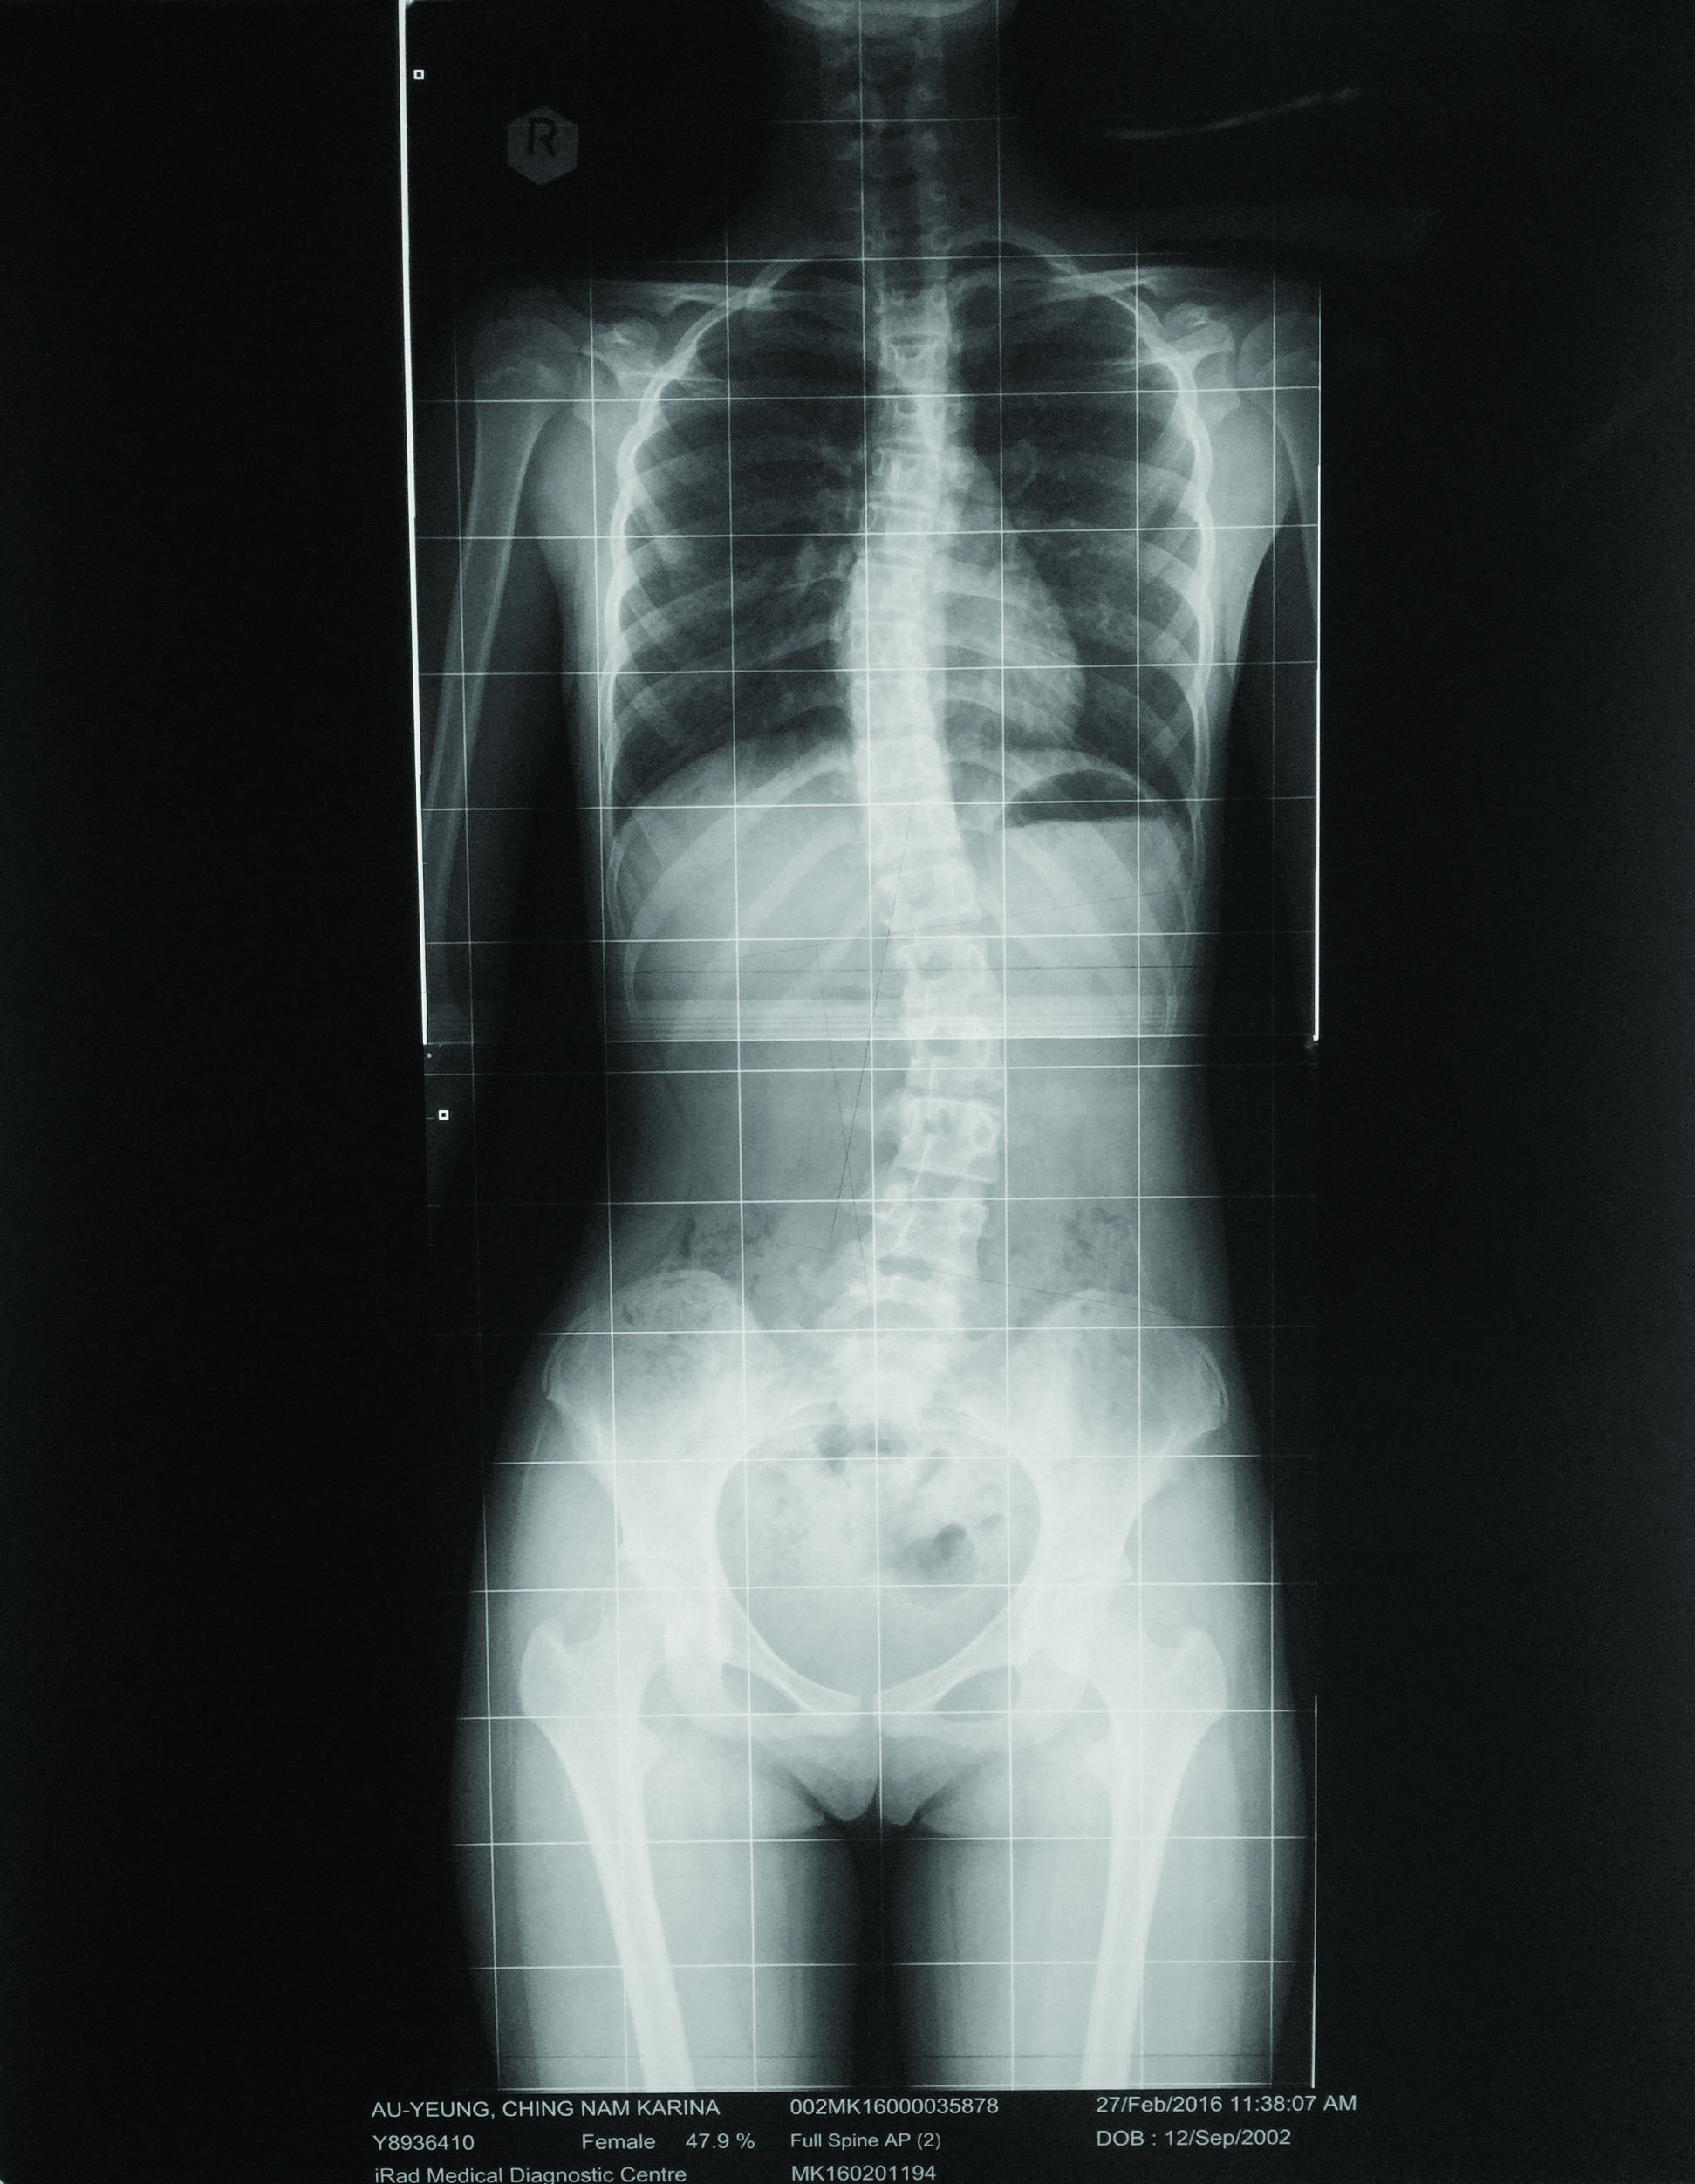

Adolescent idiopathic scoliosis (AIS) is the most common 3-dimensional spinal deformity in youths. An innovative tank-top, which features a biofeedback system with multiple sensors, has been invented to provide back muscle and customized posture training for scoliosis patients.